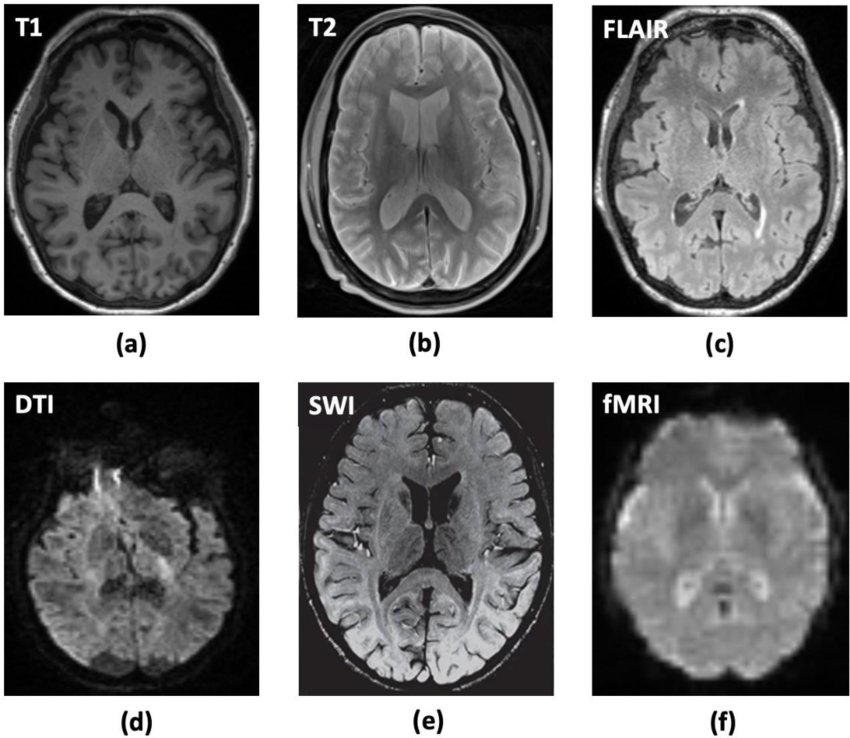

MRI can be categorized into several types, each designed to provide specific information about the body’s structures and functions as shown in Fig. 2.

• Structural MRI:

• T1-weighted MRI: These images provide high-resolution anatomical detail [34]. T1-weighted imaging sequences are particularly effective for highlighting fat-rich tissues and evaluating normal anatomical structures. These sequences generate high-intensity signals for tissues with high fat content, while fluid-filled structures appear with lower signal intensity, providing distinct contrast for diagnostic assessment.

• T2-weighted MRI: T2-weighted imaging is highly sensitive to variations in water content within tissues, making it a valuable tool for detecting pathological conditions such as tumors, inflammatory processes, and edema. [34]. These images enhance the contrast of fluid-rich regions, aiding in precise diagnostic evaluations.

• Fluid-Attenuated Inversion Recovery (FLAIR): FLAIR is a specialized MRI sequence that suppresses the signal from cerebrospinal fluid (CSF), making it easier to visualize lesions and abnormalities in the brain [35]. It is particularly useful for detecting white matter lesions.

• Diffusion MRI: This technique evaluates the diffusion of water molecules within tissues [36]. It is particularly useful for imaging brain white matter tracts, as it provides insights into the integrity of neural pathways.

• Diffusion Tensor Imaging (DTI): A specialized form of diffusion MRI that characterizes the directionality of water diffusion [37]. DTI allows for the visualization of white matter tracts, which is essential in studying conditions like stroke and multiple sclerosis.

• Susceptibility Weighted Imaging (SWI): SWI is an advanced MRI technique that enhances the visualization of blood vessels and detects small hemorrhages by utilizing phase information from the MR signal [38]. It is particularly valuable in identifying vascular malformations and assessing traumatic brain injuries.

• Functional MRI (fMRI): fMRI measures brain activity by detecting changes in blood flow related to neural activity [39]. When a brain region is active, it consumes more oxygen, leading to changes in the blood’s oxygenation level. fMRI can be used for pre-surgical brain mapping, studying brain functions, and assessing neurological disorders.

Refer to caption

Figure 2: Brain MRI - a non-invasive high-resolution medical imaging modality taken from [40] Fig. 2(a) T1-weighted MRI, 2(b) T2-weighted MRI, 2(c) Fluid-Attenuated Inversion Recovery (FLAIR), 2(d) Diffusion Tensor Imaging (DTI), 2(e) Susceptibility Weighted Imaging (SWI), 2(f) Functional MRI (fMRI)